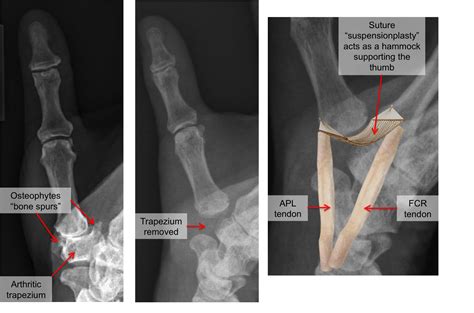

A bone spur is a smooth, hard bump of extra bone that grows along the edges of a joint. When it occurs in the wrist, it is almost always a sign of underlying joint damage, most commonly from osteoarthritis. As the protective cartilage that cushions the ends of your bones wears away, the body attempts to repair the damage by creating new bone. Unfortunately, this process often results in these abnormal growths rather than a smooth joint surface.

These spurs can restrict the range of motion in your wrist, cause inflammation in the surrounding soft tissues, and press against nerves or tendons, leading to significant discomfort. They are most commonly found in the joints where the wrist bones meet the bones of the hand (carpometacarpal joints) or at the site of previous wrist fractures.

• Debridement (Bone Spur Removal): The surgeon removes the bony outgrowth to restore smooth motion and relieve pressure on nearby structures.

• Joint Fusion or Reconstruction: In cases of advanced arthritis, more complex procedures might be necessary to stabilize the wrist and permanently eliminate pain.